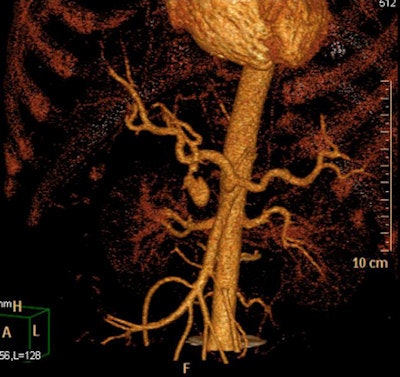

A full clinical evaluation of the patient is essential, and information about the etiology of the pseudoaneurysm, hemodynamic stability, and anticoagulation therapy is important. Studying the characteristics of the pseudoaneurysm is important, including anatomical localization, the size of the pseudoaneurysm sac, size of surrounding hematoma, diameter of pseudoaneurysm neck, vascular territory (superficial or deep/visceral) that the pseudoaneurysm arises from, and the type of end artery (expendable or inexpendable) in which the pseudoaneurysm is located. Ultrasound and CT angiography can determine all these features, although conventional angiography is used most of the time as a prelude to endoluminal treatment of the pseudoaneurysm, they stated.

radiopaedia.org/cases/gastroduodenal-artery-pseudoaneurysm.

A false aneurysm -- another term for a pseudoaneurysm -- is when there is a breach in the vessel wall such that blood leaks through the wall but is contained by the adventitia or surrounding perivascular soft tissue, according to Dr. Yuranga Weerakkody and Dr. Donna D'Souza et al, writing on radiopaedia.org. A direct communication of blood flow exists between the vessel lumen and the aneurysm lumen through the hole in the vessel wall. The risk of rupture is higher than that of a true aneurysm of comparable size due to poor support of the aneurysm wall, and thus false aneurysms generally require treatment.